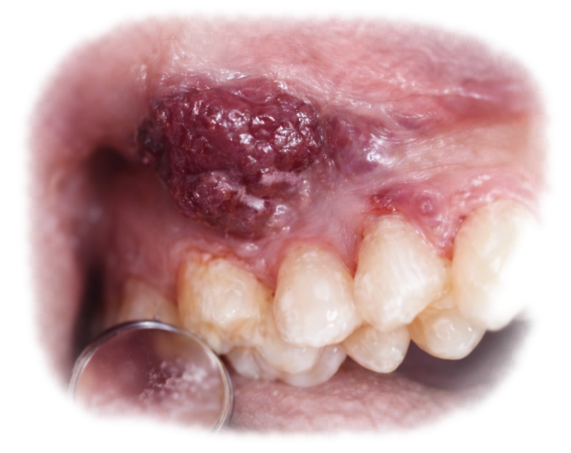

Fattori Moderni che Alterano l’Equilibrio Naturale

La rivoluzione industriale alimentare ha modificato profondamente questo equilibrio fisiologico.

Ridotta Stimolazione Masticatoria

Alimenti morbidi, ultra-processati e altamente raffinati:

- Richiedono meno masticazione

- Stimolano meno il flusso salivare

- Aumentano l’adesività sulle superfici dentarie

Questo riduce l’efficacia dei meccanismi fisiologici di autodetersione.